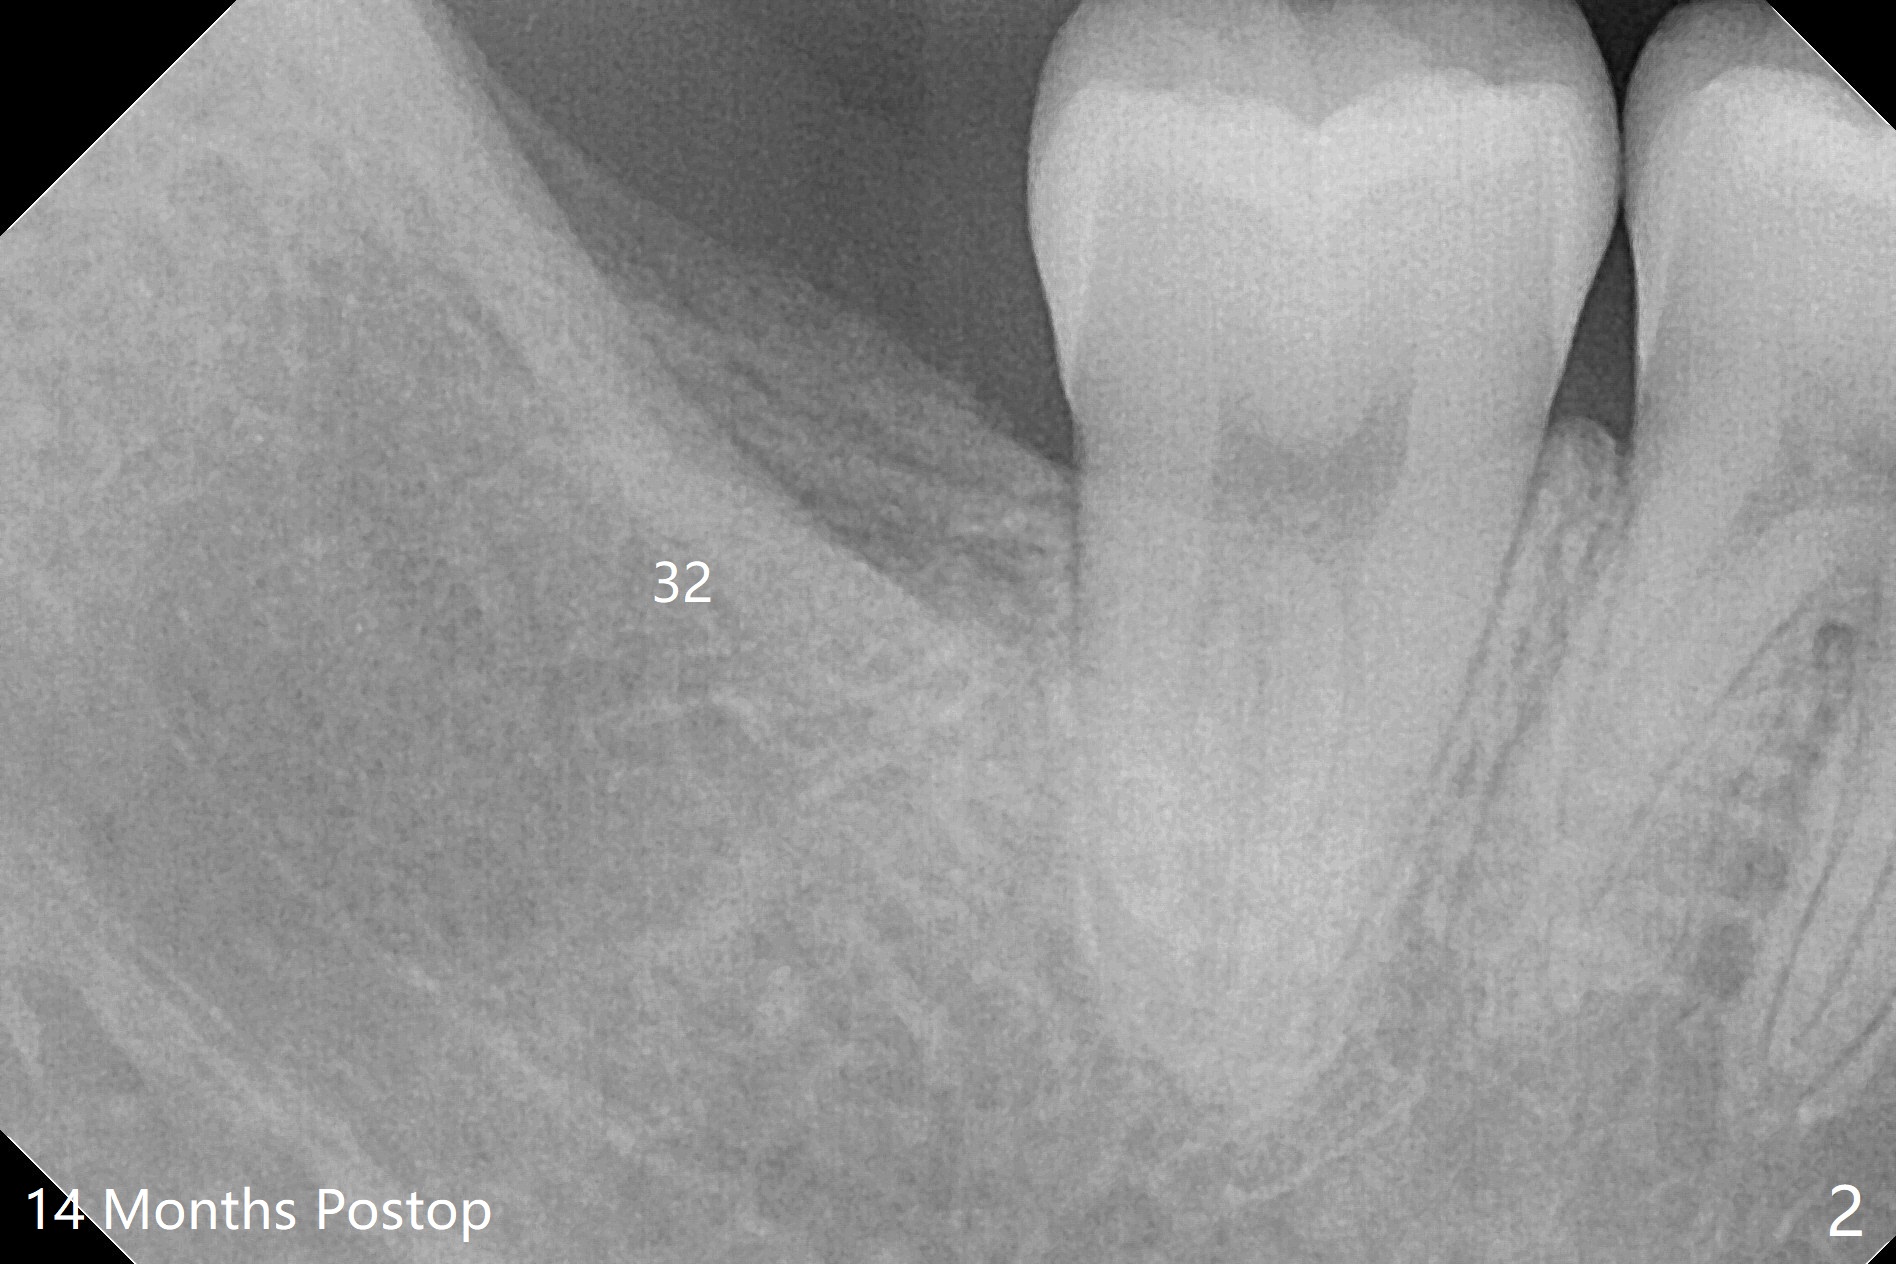

Sockets Post Osteogen Plug Placement

A 18-year-old woman has four of the 3rd molars extracted with placement of Osteogen Plug at #17 and 32 (Fig.1). Sockets seem to have healed 14 months postop (Fig.2,3).